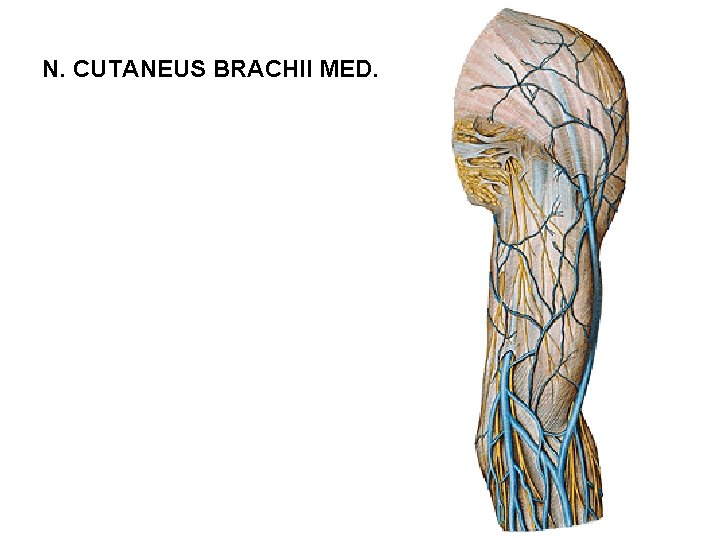

N. CUTANEUS BRACHII MED.